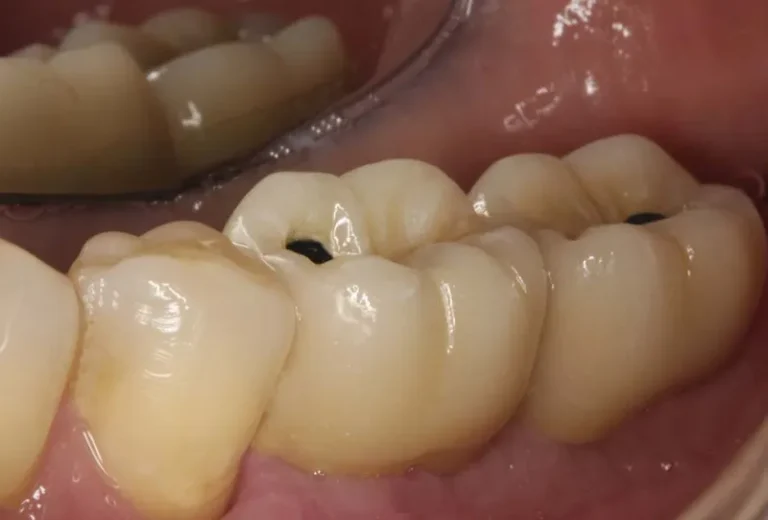

Los implantes dentales y los dientes naturales presentan características únicas que los diferencian tanto en estructura como en funcionamiento. Mientras los dientes naturales cuentan con ligamentos periodontales que proporcionan sensibilidad y capacidad de adaptación, los implantes se integran directamente al hueso mediante oseointegración. Esta distinción fundamental influye en aspectos como la sensibilidad a la temperatura,…

Mantener unas encías saludables es fundamental cuando tienes implantes dentales, ya que la longevidad y el éxito de estos dependen directamente de la salud del tejido gingival que los rodea. La higiene adecuada, el uso de herramientas específicas como cepillos interdentales y una técnica correcta de limpieza son esenciales para prevenir la periimplantitis y otras…